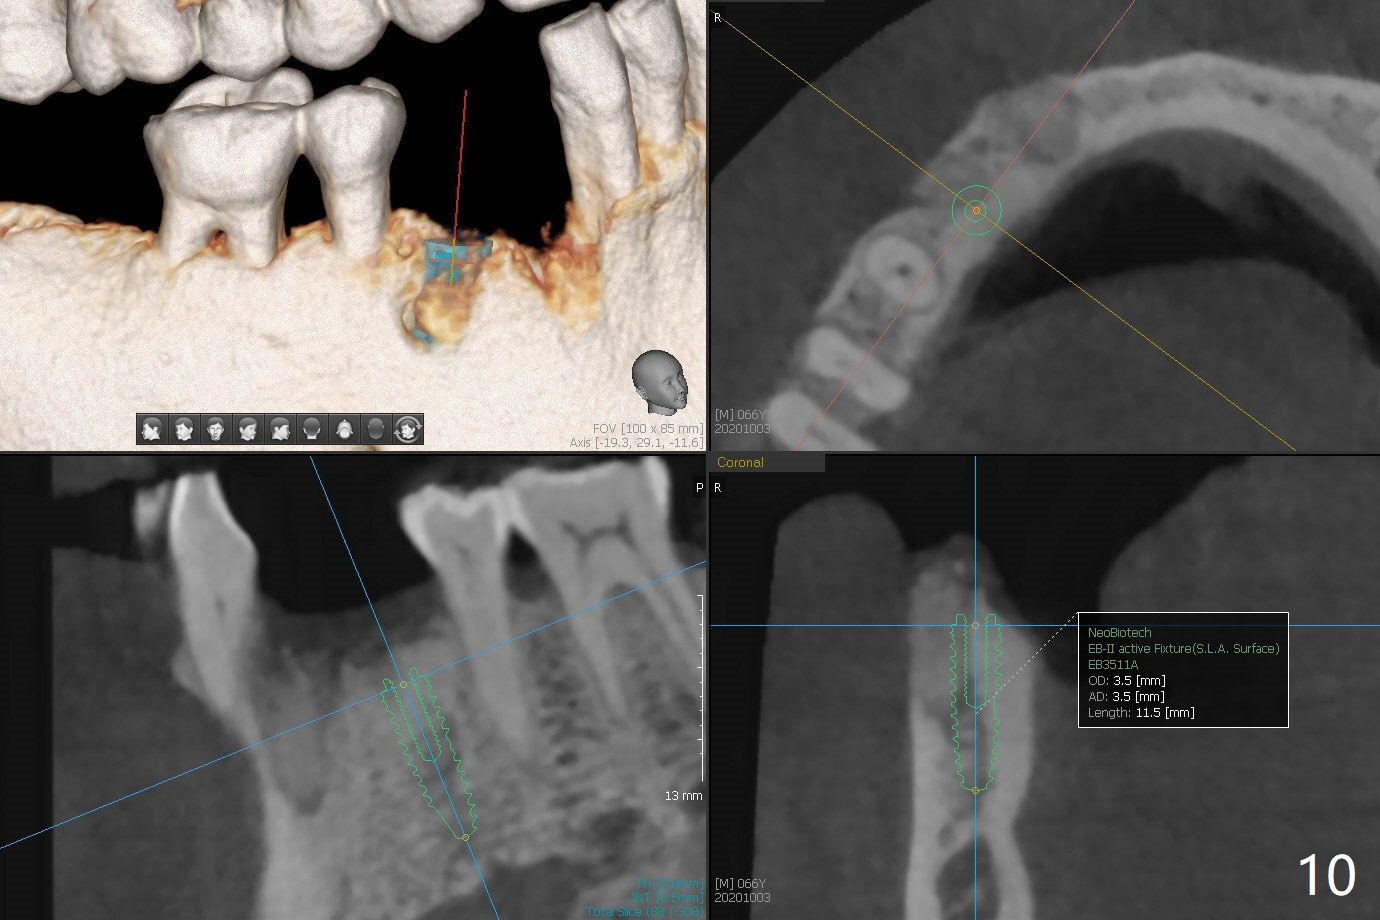

66岁男1.5年前来诊所拍摄全景片(图一),似乎27,28号牙还能保留,今天突然回来,主诉27、28区疼痛瘘道,商量决定先拔除27,28,32及右下深洗。拔除32号牙时发现它接近31区(将要植牙),必须植骨(近中部分(远中塞入胶原塞)),27,28颊侧骨板缺失(大量肉芽组织),植骨理所应当,而且必须拼命推压,但愿推到颊侧骨板,细的皮质骨没有压制感,非要加入粗的松质骨皮质骨,一张12x12毫米胎盘膜剪成两片覆盖27/28和32拔牙窝,4-0 PGA缝线固定,拍摄术后半侧全景片后(图二 (*:骨粉)),使用牙周敷料保护伤口。术后一个月27,28号牙位骨粉保持原位,而且颊侧骨板好像已经重建(图八,十一,九),似乎能植入两个植体(图十,十二)。

Since the distal crest is low at #19 after extraction (Fig.3), a 4.5x11 mm FC implant (Fig.4 green) will be immediately placed in the mesial socket (lingual), which has more clearance from the Inferior Alveolar Canal (yellow). Sticky bone will be initially up to the implant plateau, followed by insertion of a cemented abutment (pink), placement of the 2nd round of bone graft (red) and fabrication of an immediate provisional (white). To save time, a piece of collagen plug is inserted into the apical portion of the distal socket (blue). The distal crest will be expected to increase ~ 3 mm by the procedure mentioned above. The #32 socket heals with apparent exposure of collagen plug 2 weeks postop (Fig.5). The #27 and 28 sockets heal with fresh granulation tissue 2 weeks postop (Fig.6). The fistula buccal to #28 socket appears to have shrunken 2 weeks postop (Fig.7).